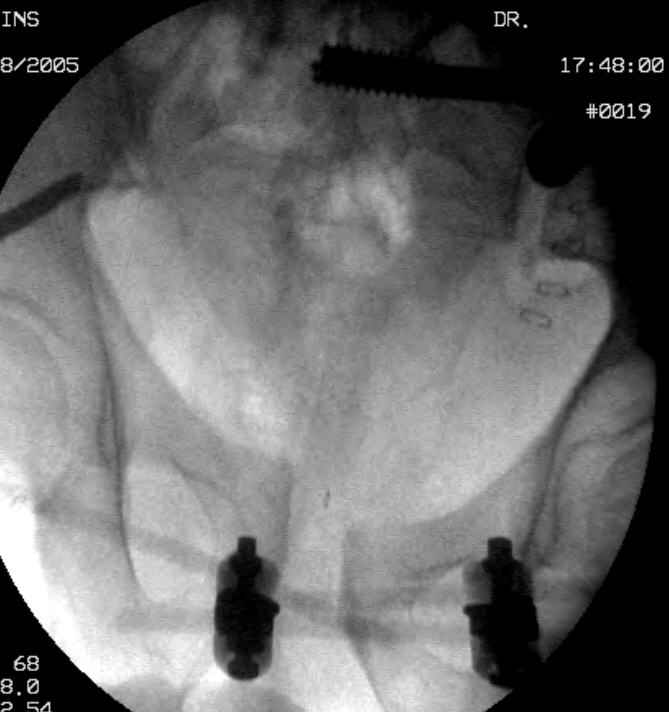

Hello gentlemen- Case is 52 YO male, fell out of treestand while deerhunting. He is 6 ft, approx. 260-275 lbs. Was hemodynamic unstable at local ER, sent to our Trauma center where circumferential pelvic binder placed and pt. stabilized with fluid, blood, and rewarming. Angiography not performed. An extraperitoneal bladder disruption was found, uro elected to treat non-operatively. Initial xray (not shown) demonstrated 5-7 cm wide at symphysis and SI joint. The first image attached is of CT once binder is in place. On post trauma day 5 the pt was taken to OR for ORIF of his iliac wing fracture and SI dislocation. The swelling/3rd spacing of fluid in the area of symphysis was profound, but quite acceptable posteriorly. Patient was prone for procedure, as I thought too difficult to fix the wing in lateral position. Of course the repair of wing was easy, but reduction of SI very demanding. The Floro images document the residual lack of reduction. That was the closest I could get it using 6mm joystick in wing, and clamp on sacrum and clamp through notch. The fixation was (initially) rigid. Anterior ex fix with supra-acetabular pins was placed due to condition of soft tissues, massive "beer-belly" overhanging the crest. Post trauma day ten patient's xray shows failure of posterior construct. Plan was to perform revision orif once soft tissues resolve considerably for full anrterior fixation and posterior fixation. However, while Im away for holiday (on Post trauma day 15), pt is developing septic clinical appearance, and trauma suspects pelvic abcess near symphysis and performs I and D - finds nothing but no primary closure performed. Posterior tissues/incision continue to look healthy. Now is post trauma day 17, pt is still tubed/on dopamine/and wbc still elevated, anterior incision still packed open. Clearly must get to bottom of possible sepsis, but then what? Thanks for you time - sorry for such lengthy clinical description. Thomas Schaller Kalamazoo, Michigan

Request for more images.. Axial and coronal recon (pt in binder.)